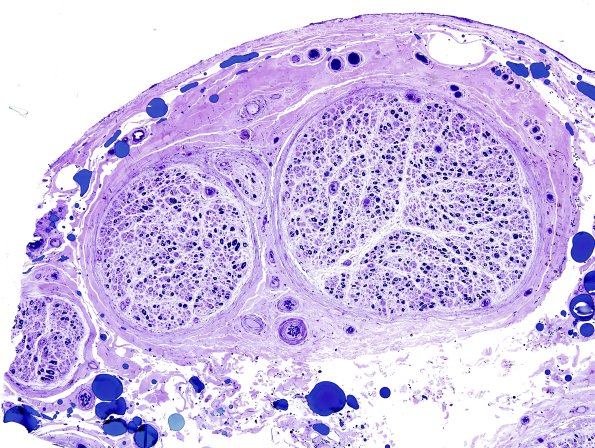

Washington University Experience | PERIPHERAL NEUROPATHY | 13 POEMS SYNDROME | 4A1 POEMS (Case 4) Plastic 5.jpg

4A1,2 The low magnification plastic section images show moderate loss of large and small myelinated axons. (Plastic sections)